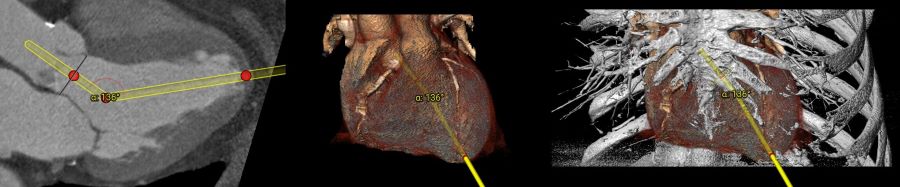

transapical.jpg

A transapical TAVI involves the insertion of a catheter through the chest wall. It will then be guided to the tip of the heart or the existing aortic valve. Here are some potential advantages associated with a transapical TAVI:

A typical TAVI will require an insertion to be made at the femoral artery. A catheter and the replacement valve will then be guided to the region where it is intended to be placed. There can still be times when a femoral insertion is deemed too risky (such as if the patient has existing vascular issues). In this instance, a transapical TAVI may be the best solution.